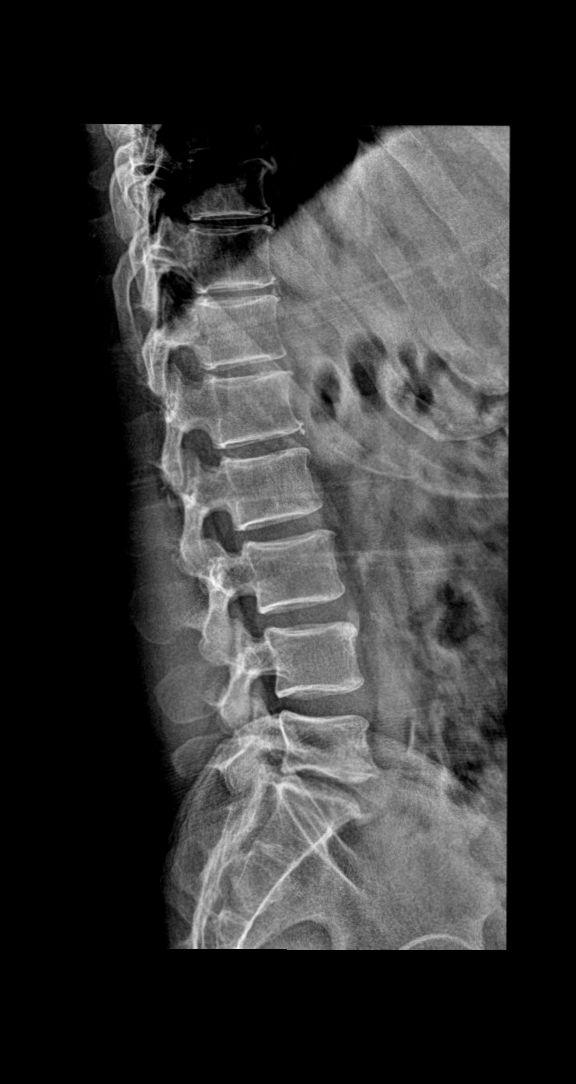

来了来了ok 大家踊跃参与讨论 患者主诉:男 52y 下肢麻木 酸疼 考虑什么家人们